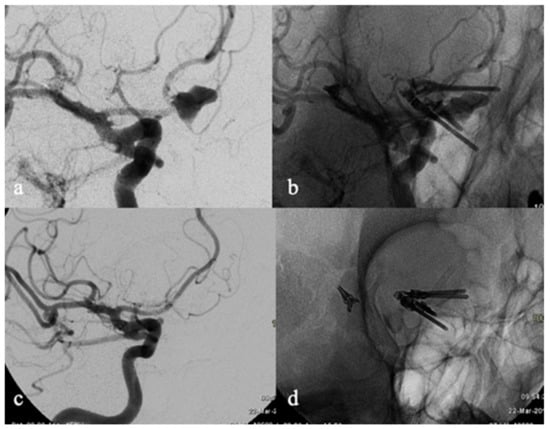

- Brinjikji, W.; Piano, M.; Fang, S.; Pero, G.; Kallmes, D.F.; Quilici, L.; Valvassori, L.; Lozupone, E.; Cloft, H.J.; Boccardi, E.; et al. Treatment of ruptured complex and large/giant ruptured cerebral aneurysms by acute coiling followed by staged flow diversion. J. Neurosurg. 2016, 125, 120–127. [Google Scholar] [CrossRef]